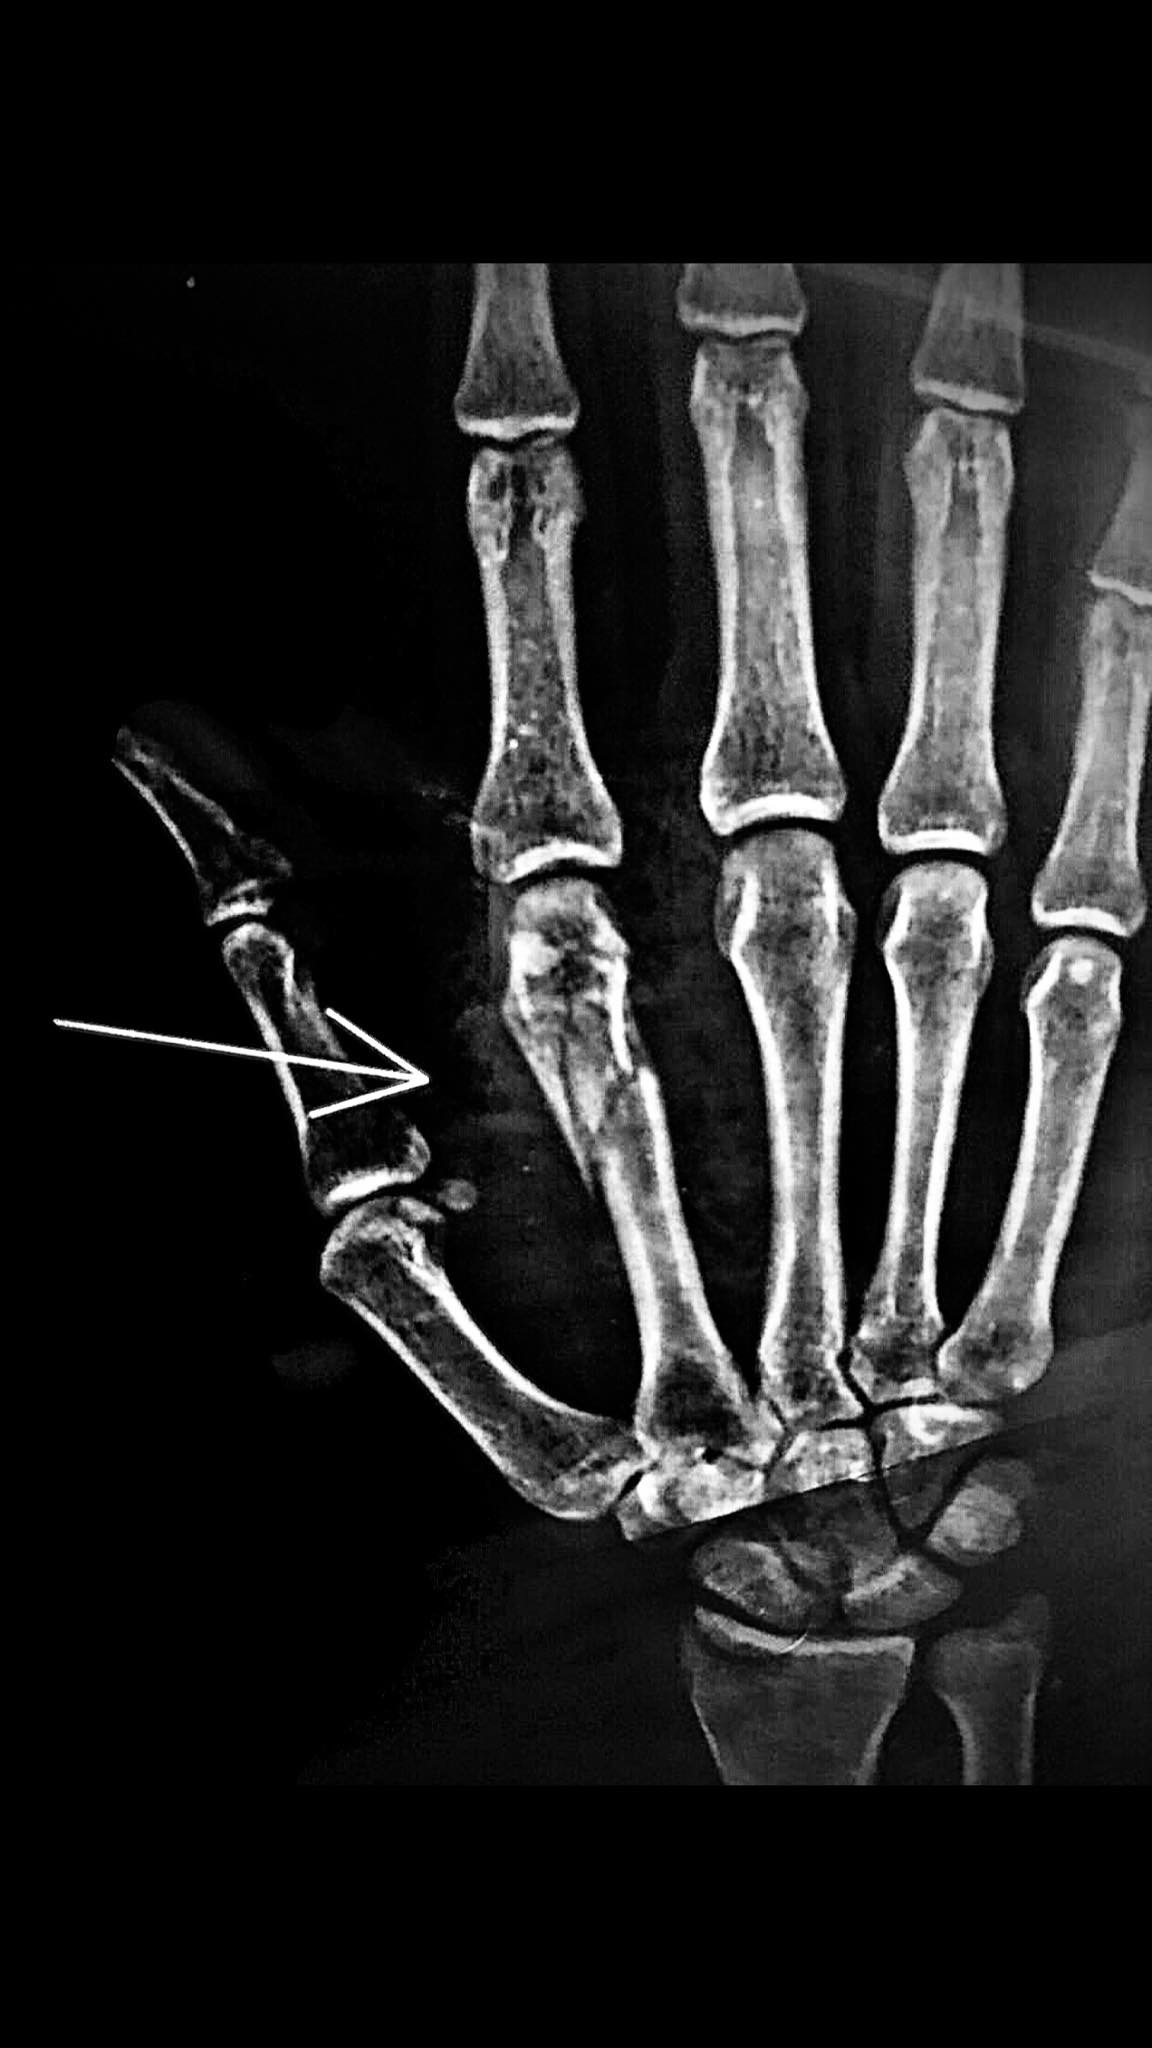

I had an accident and my 2nd Metacarpal Bone of my right hand got fracture. When I tried making fist right after accident, my index finger had malrotation towards middle finger. My doctor saw xrays and did hard plaster. How long will it take to recover estimated? Am I gonna have rotation issue after plaster is removed? Its been 10 days. Should I do something about it or wait for new xray prescribed after 2-3 weeks of plaster/injury.